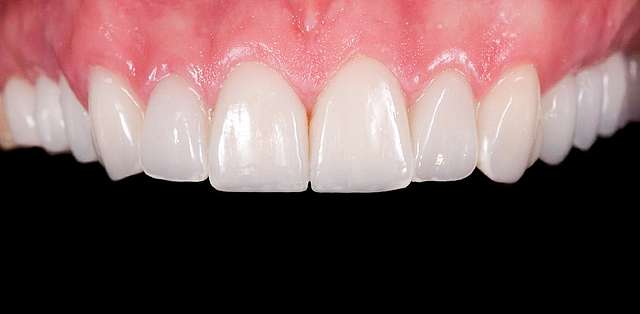

A mock-up is the visual side of a treatment plan. Consider the treatment plan as something scriptic, that contains price estimates and procedures, some hard to understand. Consider the treatment plan as the text , whereas the mock-up is the drawing meant to explain it. Traditionally the mock-up was used to test prosthetic design of a future restoration. In present times the mock-up is used at the beginning of most rehabilitations to express visually the esthetic impact of the proposed treatment plan. The entire process is non invasive and reversible. The mock-up is transferred on top of the existing teeth, whenever possible , and a series of optical ilusions is used in order to simulate the future smile. Generally it is communicated to the patient via pictures or videos, that will serve as the draft for communication between patient and the team treating him.

The mock-up just like a treatment plan can simulate a diverse array of procedures that vary on cases basis. In this case, we have dental implants and tissue grafts in posterior areas, on both sides, and ceramic veneers and crown lengthening in anterior side to balance the smile. As a fine detail , you can see how the dentist uses a black marker to simulate the area of the tooth which will be reduced. The mock-up, once accepted becomes a cental pillar in an interdisciplinary treatment. It will be used to determine how the gums will be remodelled , where the implants should be placed, and how the teeth need to be prepped for the future restorations.